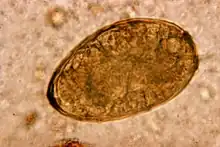

Egg of Paragonimus westermani